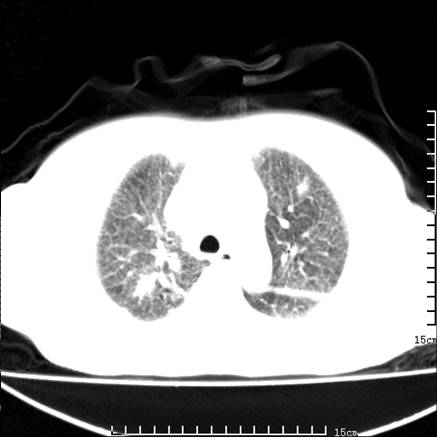

女,王某,58岁,咳嗽三个月余,基层医院二个月前诊为肺结核,用抗结核药二个月无明显疗效。

双肺继发型tb,心功能不全并肺淤血、心包、双侧叶间裂积液,肺大泡,右下胸膜肥厚钙化。

肺窗真难看,建议重做!